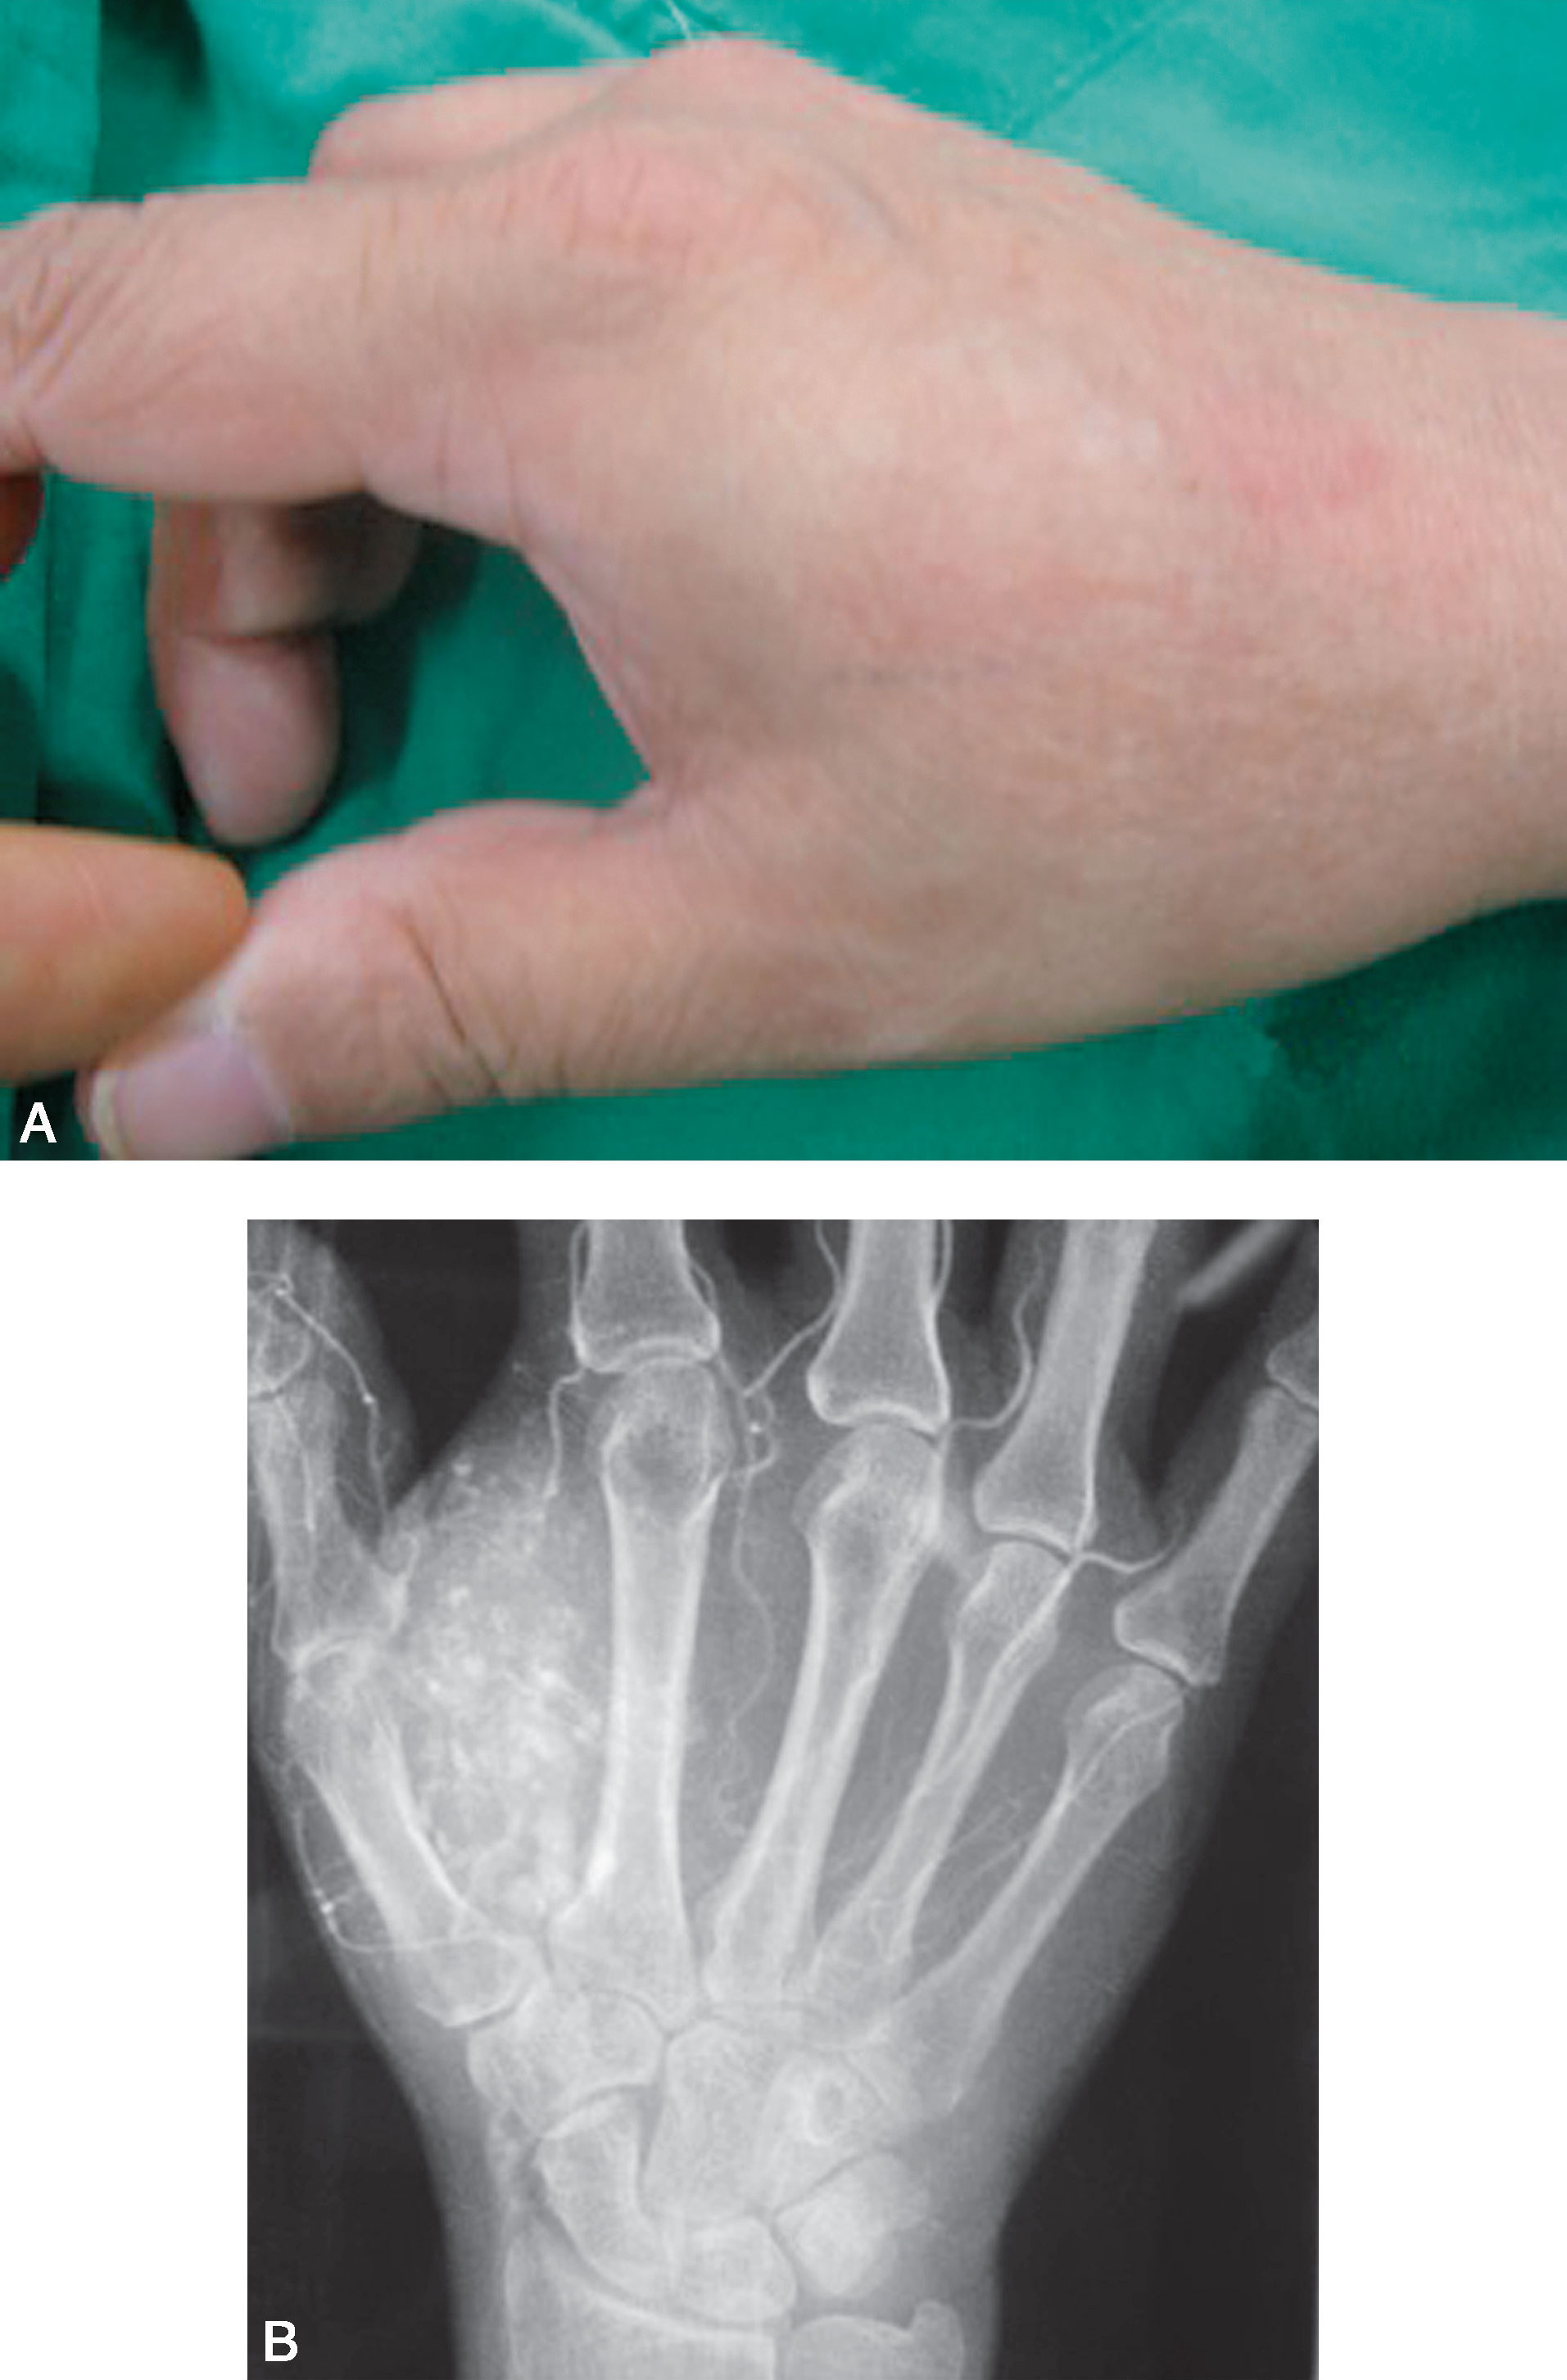

图1-2-31 海绵状血管瘤病例

A.手体位像显示右手拇指蹼内有界限不清的肿物;B.X线片显示右手拇指蹼内海绵状血管瘤、散在的静脉石

(2)海绵状血管瘤(图1-2-31、图1-2-32)。